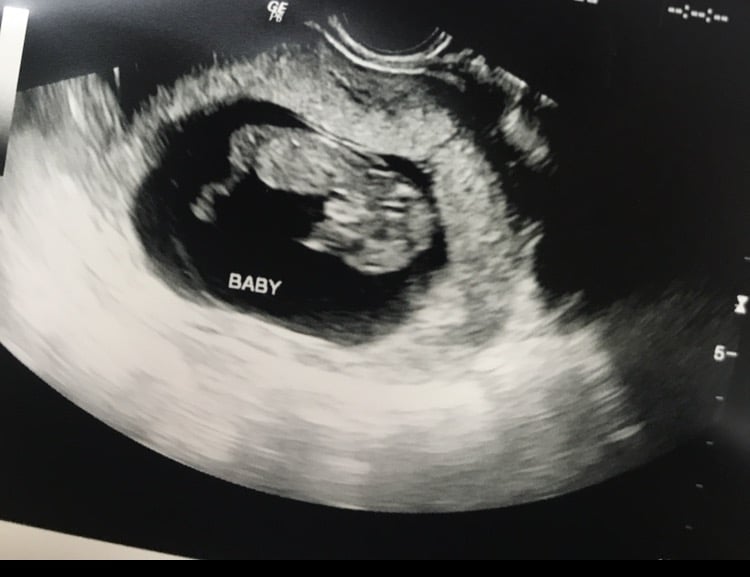

I'm 12w5d but measuring at 13w4d (!!!) I got to see my little bean bouncing around all over the place, and moving it's arms all over.

ETA picture since it didnt post the first time